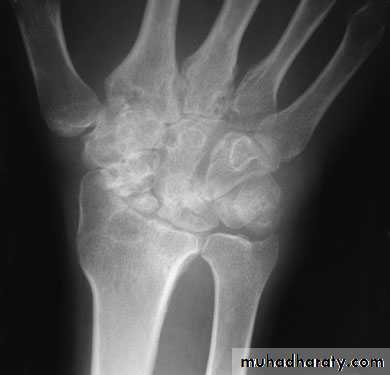

1-Avascular necrosis The proximal fragment may die,especially with proximal pole fractures, and then at 2–3 months it appears dense on x-ray.2-Non-union By 3 months it may be obvious that the fracture will not unite with sclerosis and cavitation. Bone grafting with compression screw should be attempted, especially in the younger, more vigorous type of patient, because this probably reduces the chance of later, symptomatic osteoarthritis.

3-Osteoarthritis: Non-union or avascular necrosis may lead to secondary osteoarthritis of the wrist.

The treatment either by wrist arthrodesis or proximal raw carpectomy.